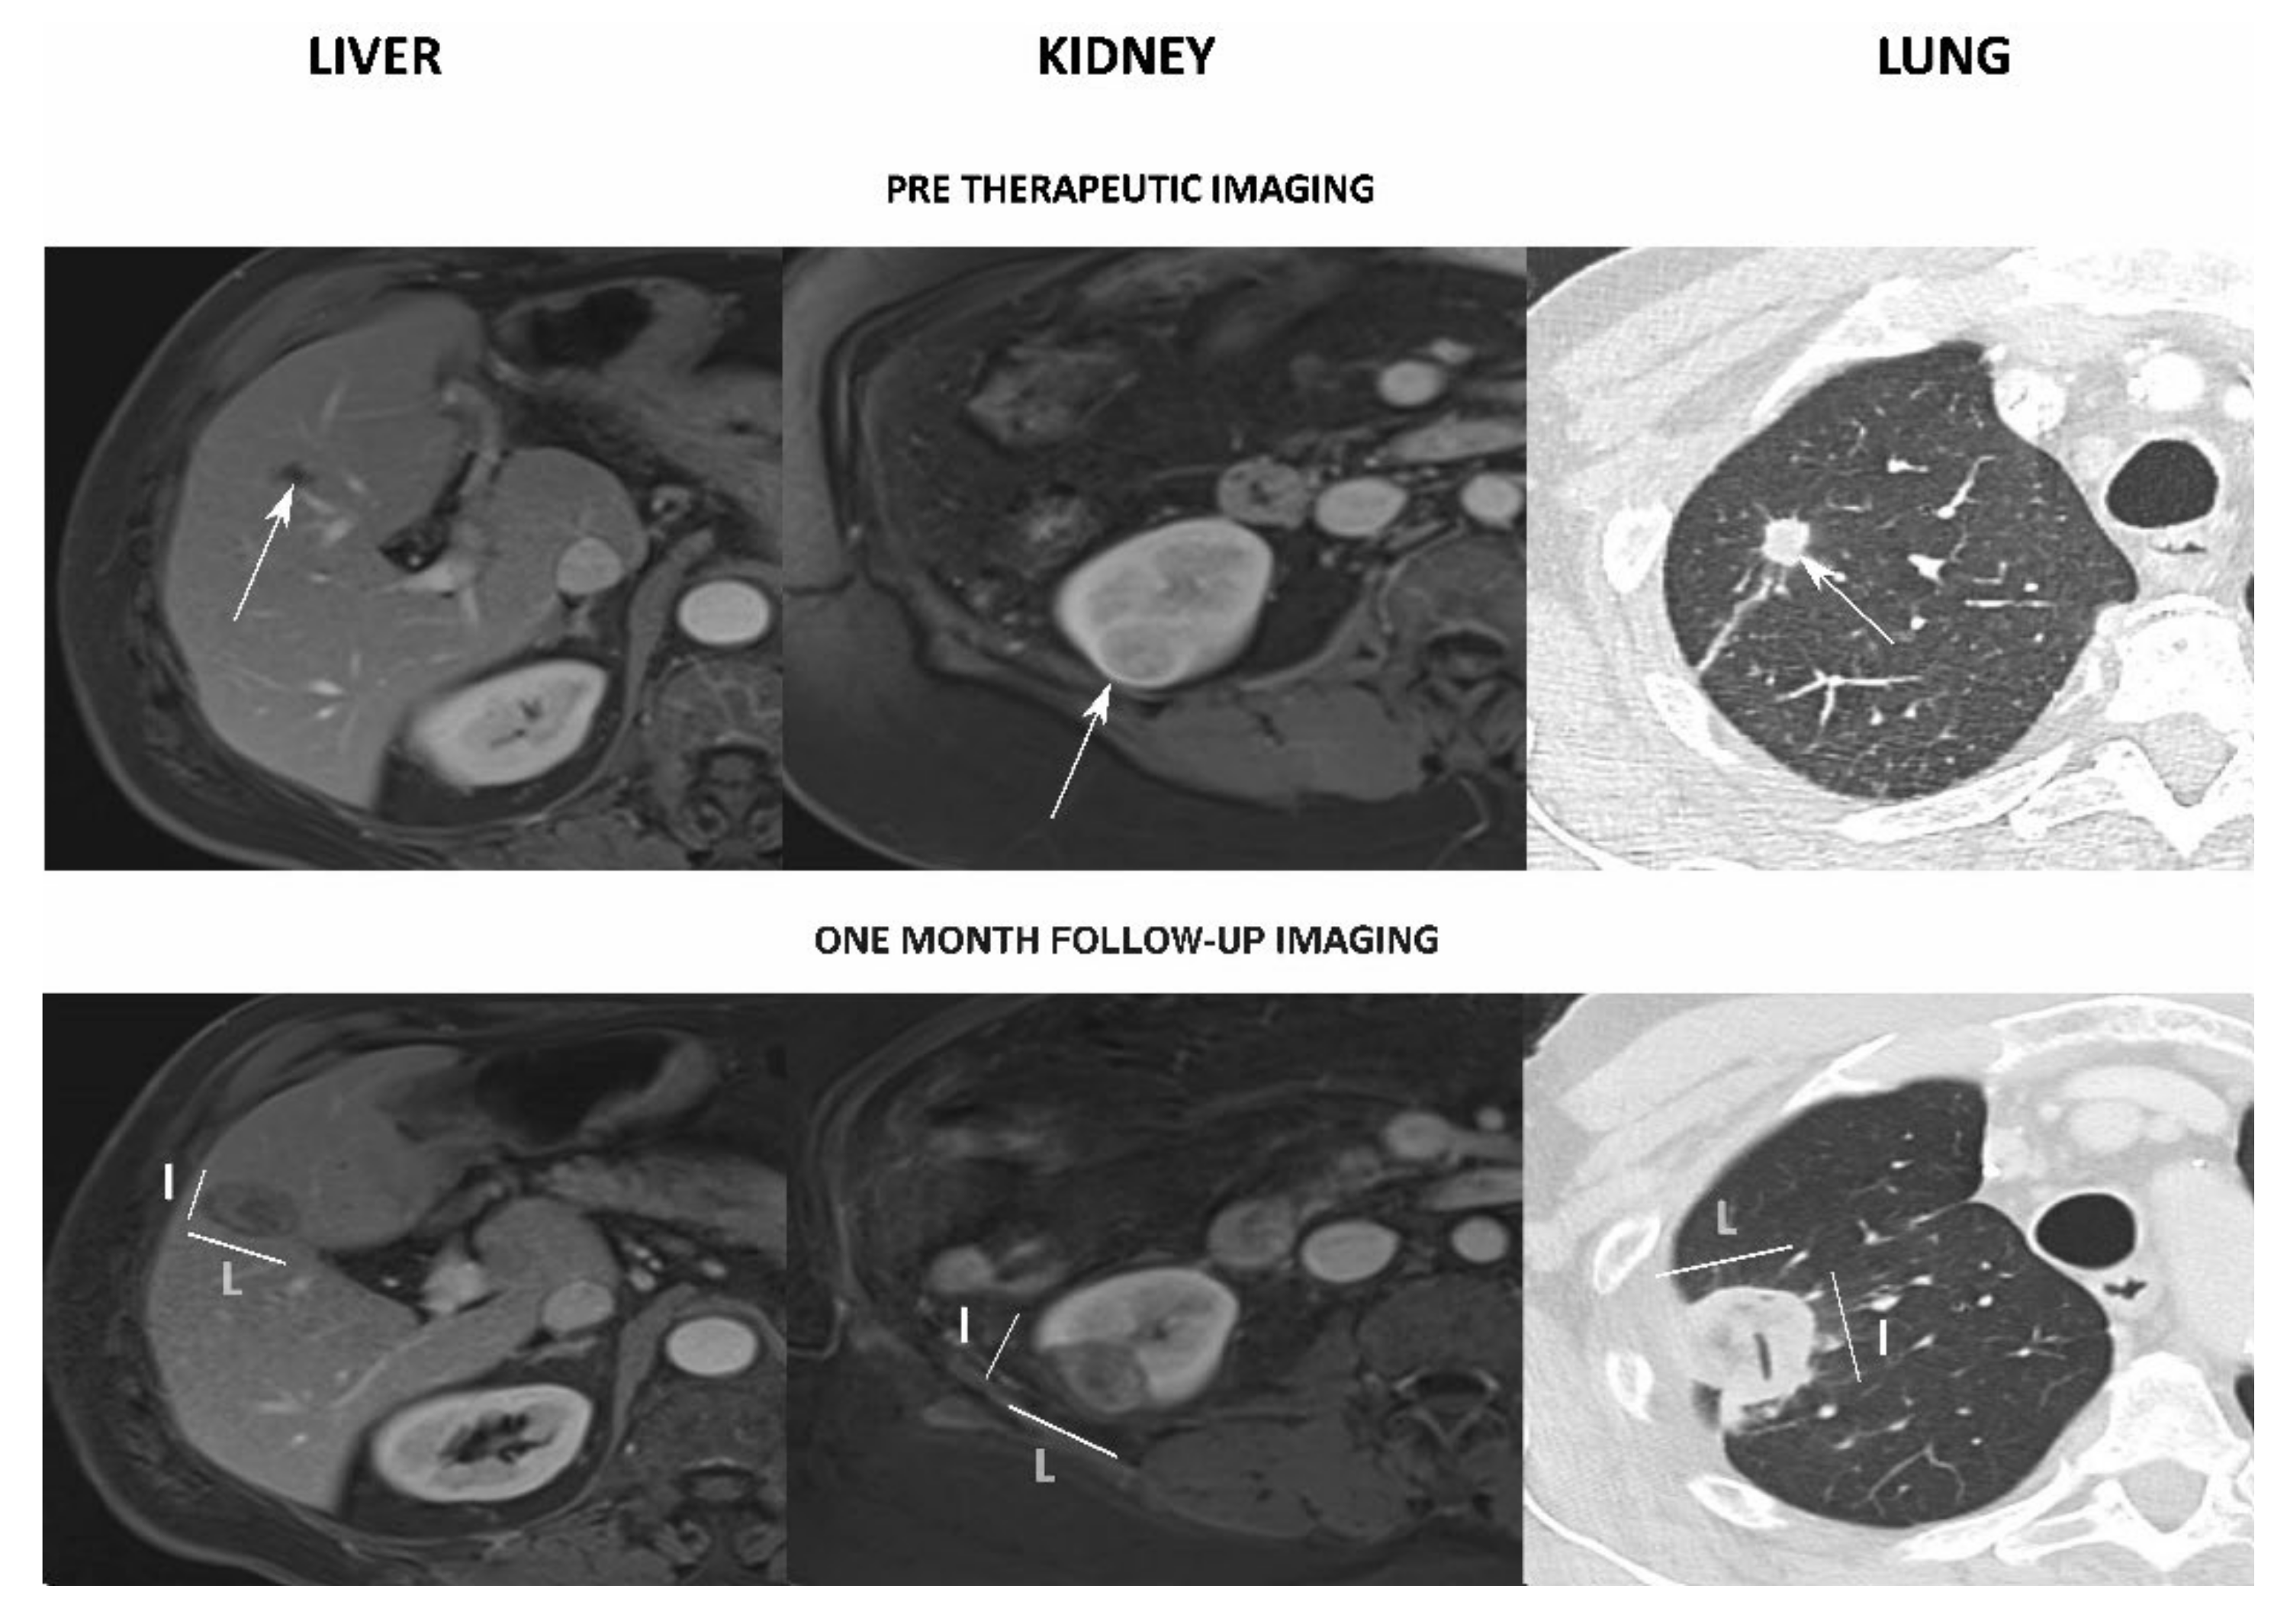

Figure 2.

Examples of assessment of the ablation zones for liver (left), kidney (middle) and lung (right) lesions. Top: pre-treatment assessment of the target lesion (white arrows). Bottom: assessment on the one-month follow-up imaging, with the major (L) and minor (l) axes measurements. Note: air was found inside the ablation zone (tubular structure).

The ablation zones data are presented in Table 3, and 73% of the measurements were performed on MRI. The Bland–Altman analysis results for L and l are presented in Figure 3. Concerning liver lesions, 28 patients (28/31, 90%) with 58 ablations (58/63, 92%) underwent an MRI, and 3 patients (3/31, 10%) with 5 ablations (5/63, 8%) had a CT scan performed at a median time of 32 ± 7 days (range: 22–48) after treatment. The results of the Bland–Altman test showed a good agreement with a subtle, smaller, less spherical ablation zone than expected according to the manufacturer’s chart: −2 ± 5.7 mm for L, −5.2 ± 5.6 mm for l, −0.15 ± 0.18 for the SI. Correlations were moderate for L (r = 0.69, p < 0.001) and l (r = 0.59, p < 0.001). There was no correlation for SI (r = 0, p = 0.99).

For kidney lesions, 12 patients (12/13, 92%) with 13 ablations (13/14, 93%) had an MRI and 1 patient (1/13, 10%) with 1 ablation (1/14, 7%) had a CT scan performed at a median time of 32 ± 8 days (range: 12–50) after treatment. The Bland–Altman test showed a moderate agreement with a bigger and less spherical ablation zone than expected: +8.69 ± 7.94 mm for L, +0.36 ± 4.77 mm for l, −0.28 ± 0.27 for the SI (Figure 2). There were no significant correlations for L (r = 0.41, p = 0.14), l (r = 0.48, p = 0.08) or SI (r = −0.36, p = 0.21).

For lung lesions, 11 patients (11/11, 100%) with 18 ablations (18/18, 100%) had a CT scan performed at a median of 32 ± 6 days (range: 15–47) after treatment. A moderate agreement with a smaller, less spherical ablation zone than expected was found using the Bland–Altman test: −5.45 ± 4.5 mm for L, −9.32 ± 4.72 mm for l, −0.24 ± 0.2 for the SI (Figure 2). Correlations were strong for L (r = 0.76, p < 0.001) and l (r = 0.75, p < 0.001). There was no correlation for SI (r = 0.24, p = 0.33).